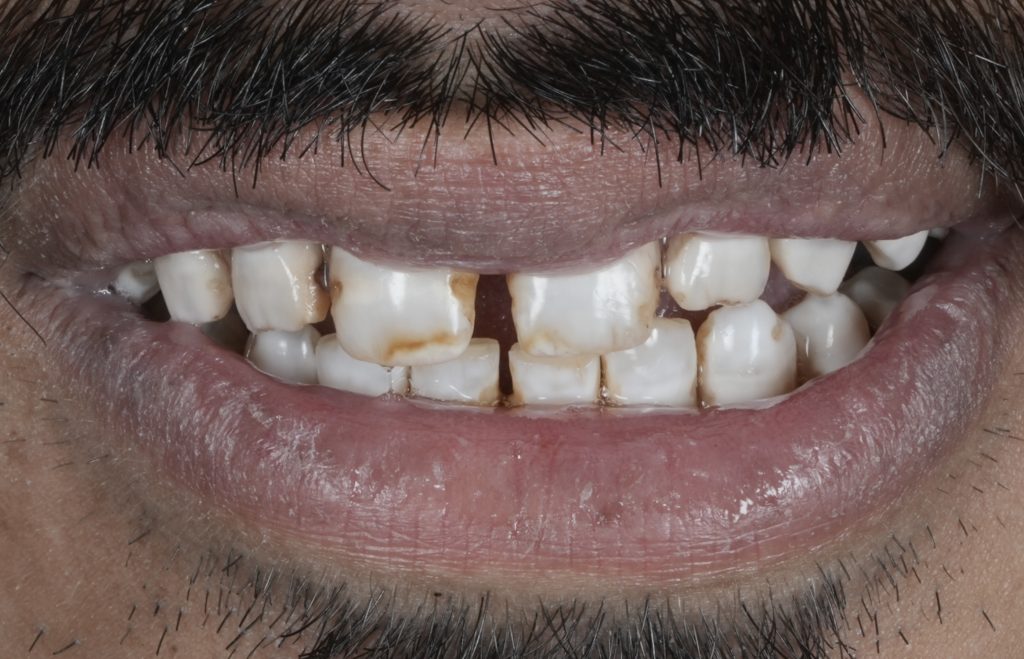

True esthetic dentistry does not begin with restorative materials or ceramic selection. It begins with understanding the condition of the enamel itself. Under proper isolation and magnification, enamel reveals a detailed narrative of demineralisation, developmental defects, discoloration, and marginal compromise that is often masked in routine clinical settings. This article highlights the importance of slowing down, isolating properly, and respecting biological principles to achieve predictable diagnosis, planning, and long-term restorative success.

Modern dentistry often moves fast. Digital workflows, restorative materials, and cosmetic demands can overshadow the most critical diagnostic step: reading the enamel. When teeth are isolated properly and viewed under magnification, enamel becomes a diagnostic map rather than a simple surface.

Demineralised zones, hypoplastic defects, marginal breakdown, and color discrepancies are frequently underestimated when examined without isolation. These subtle findings play a decisive role in treatment planning and directly influence restorative longevity.

Why Esthetics Start Before Restorations

Esthetic success is often attributed to:

- Composite layering

- Ceramic translucency

- Shade matching

In reality, esthetics begin much earlier.